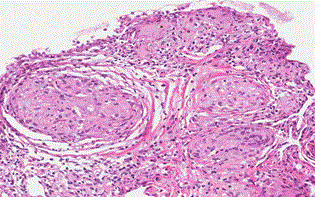

The bronchoscopy with lung biopsy was performed. Epithelioid granulomas with multinucleated giant cells and cytoplasmic mineralization, and fibrosis of surrounding tissue were found, which proved the diagnosis of sarcoidosis (Figure 2).

Figure 2: The lung biopsy (HE staining).